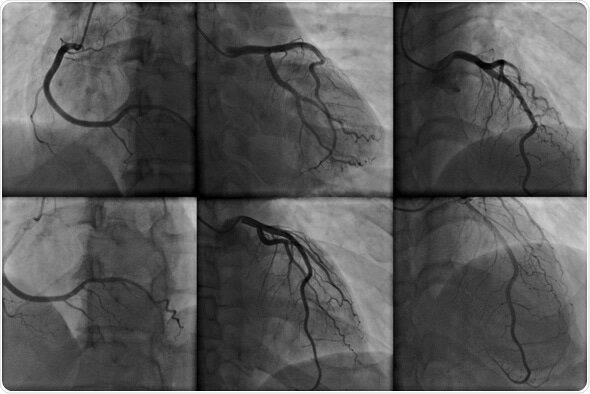

• ANGIOGRAFIA

Examen de diagnóstico por imagen cuya función es el estudio de los vasos circulatorios que no son visibles mediante la radiología convencional. Su nombre procede de las palabras griegas angeion, "vaso", y graphien, "grabar". Se puede distinguir entre arteriografía cuando el objeto de estudio son las arterias, y flebografía cuando se refiere a las venas.

• La arteriografía

Es un proceso de diagnóstico por imagen cuya función es el estudio de los vasos arteriales que no son visibles mediante la radiología convencional. Se habla de arteriografía cuando el objeto de estudio son las arterias, si fueran las venas se habla de flebografía, ámbas técnicas se agrupan en lo que se conoce como angiografía.

• La angiografía es una técnica invasiva,

Requiere la introducción de un catéter en una arteria periférica, con frecuencia se usa la arteria femoral o incluso la vena cubital. Sin embargo existen técnicas no invasivas, como la angiografía por tomografía computarizada, para detectar un número importante de patologías con la misma precisión que la técnica invasiva.